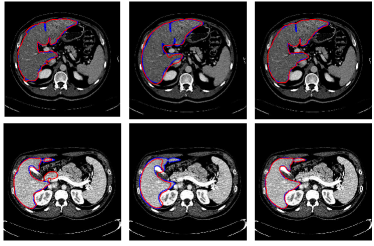

Refer to caption

Figure 6: Illustrations of the role of the likelihood liver map. From the first column to the last, outcomes of graph cut without the likelihood liver map, convolutional neural networks and the proposed integrated model for two typical images are displayed respectively in red. The ground truth is in blue

To better understand the role of the learned liver likelihood map, Fig. 6 depicts the outputs of the graph cut without the liver likelihood map, 3D CNNs and the proposed method for two typical images in red. The ground truth segmentations drawn by experts are in blue. Obviously, incorporated with the liver likelihood map, the proposed model can achieve a better agreement with the ground truth.

Figure 7 illustrates our segmentation and manual delineations for four challenging cases in coronal, sagittal, and axial planes. The initial liver region generated by 3D CNNs is in yellow, the final refined result is in red and the manual delineation is in blue. The first column shows a case with highly inhomogeneous appearances. The last three columns display three representative livers containing tumors. Particularly, some tumors locate on the boundary, which makes it more difficult to automatically delineate the accurate boundary. As can be seen, 3D CNNs can detect the most liver region and the refinement model can obtain a higher agreement with the ground truth. Figure 8 depicts the corresponding 3D visualization results of 3D CNNs and the proposed method for the cases shown in Fig. 7. The 3D visualization of errors is based on the MSD error between the segmentation result and the ground truth. As can been seen, the MSD errors of the 3D CNNs for the four cases (from left to right) are 22.1 mm, 12.6 mm, 62.6 mm and 74.5 mm, respectively, while the MSD errors of the proposed model are 17.0 mm, 11.2 mm, 22.1 mm and 15.3 mm, respectively. Obviously, the proposed approach can obtain lower errors in terms of MSD.